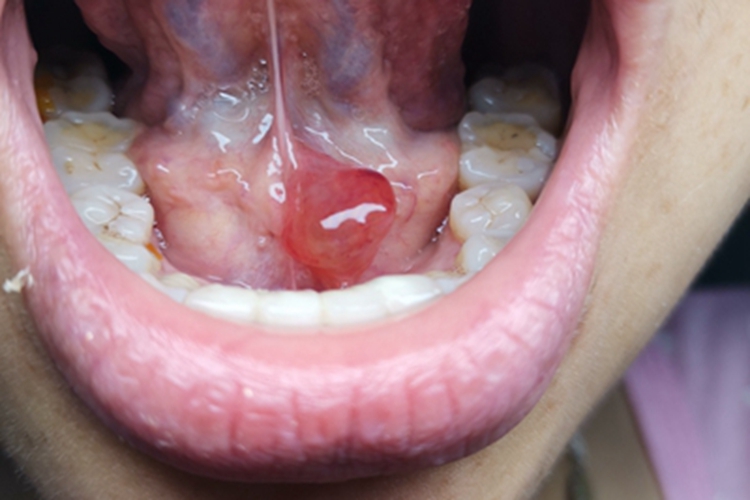

涎腺囊肿皮损可表现为疙瘩,如蚕豆大小,质地较软,表面光滑,有反光感,患者可自觉有异物感,局部可自发破溃,流蛋清样液体,常反复出现。

涎腺囊肿可发生在腮腺、颌下腺及舌下腺区,涎腺导管因炎症或结石阻塞使腺体分泌物潴留所致,阻塞原因多系损伤,有时多次反复损伤,可形成瘢痕而阻塞排泄管。